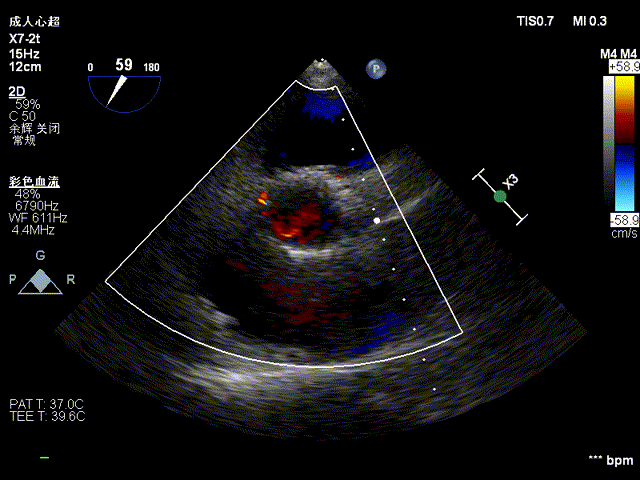

将MitraClip推进至左心室,捕获瓣叶:

捕捉瓣叶后,经超声心动图确认瓣叶夹持牢固,释放瓣膜夹:

二尖瓣反流较术前显著减少: